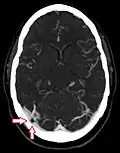

CT angiography showing an arachnoid granulation in the right transverse sinus -